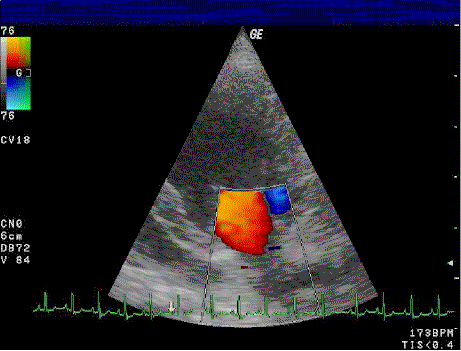

Par contre, ils nous arrivent d'utiliser un mode, le mode Doppler afin de visualiser les flux sanguins. Les flux qui se dirigent vers la sonde auront une certaine couleur tandis que ceux qui s'éloigne auront une autre couleur. Cela permet de différencier les artères et les veines par exemple.

L'échographie en mode doppler fonctionne sur ce procédé.

La sonde, c'est vous. Le sang représente le flux de voiture qui passe. Après analyse, la machine détermine le flux sanguin qui s'éloigne de la sonde et le flux sanguin qui s'en approche. Ensuite, l'ordinateur colore l'image.

Echographie doppler d'une valve mitrale

Crédit : Kalumet, from Wikimedia Commons